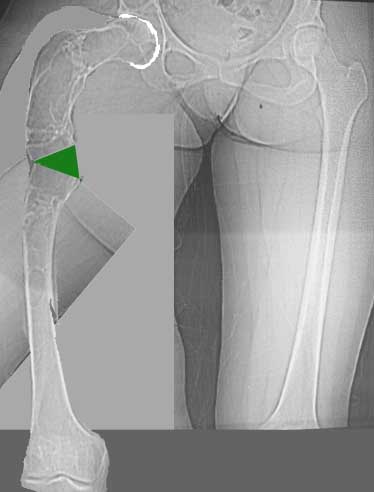

Возможна аппаратная коррекция оси с формированием клиновидного регенерата, которая решила бы и проблему укорочения (что, впрочем, нужно уточнить по схеме, сделанной по рентгенограмме с хорошим захватом смежных суставов - схемка по присланному снимку в приложении). По окончании коррекции - блокируемый стержень, который и сократит время пребывания в аппарате, и вообще возврата к нормальной жизни, а также будет мерой профилактики патологических переломов.

А может быть, если при планировании выяснится, что "открытый клин" решает все проблемы, и есть достаточное приведение в тазобедренном суставе, пойти на одномоментную операцию - чрескожная поперечная остеотомия на вершине деформации и закрытый интрамедуллярный остеосинтез.